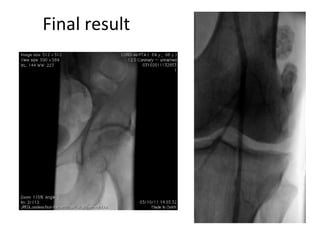

Final result

PTA of thePopliteal artery 1) Predilation with an undersized balloon 2) Prolonged dilation with a Drug Coated Balloon